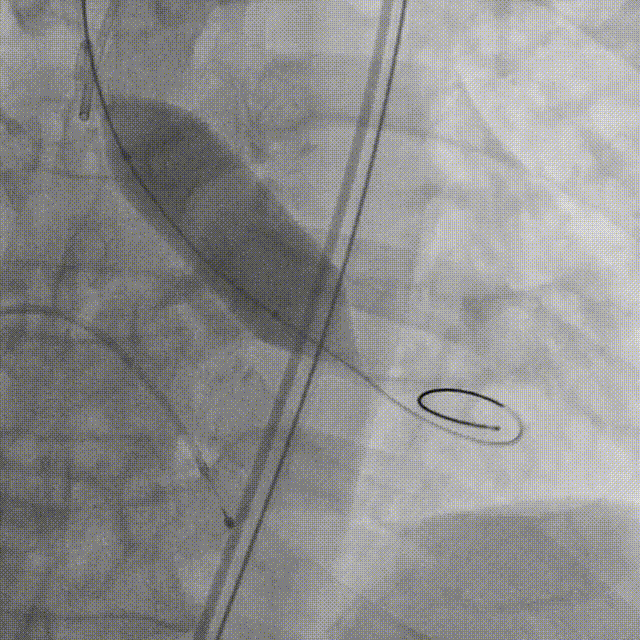

瓣膜释放到2/3的位置(手柄上有触觉提示)

瓣膜释放到80%并造影评估深度合适(少量反流,瓣膜形态椭圆)

左冠切线位造影评估冠脉风险(左冠血流灌注良好)

22mm球囊后扩张(瓣膜形态更佳)

最终造影(反流微量)